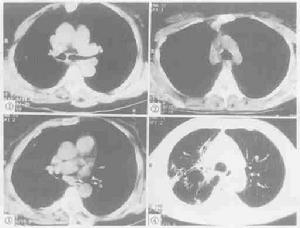

氣管、支氣管狹窄1、x 線氣管斷層攝片可發現狹窄氣管。

2、內窺鏡檢查可以有效地發現狹窄的氣管和支氣管病變。

3、氣管碘油造影檢查雖對診斷氣管狹窄及瞭解狹窄範圍均有價值,但有加重氣管梗阻的危險,值得注意。

雙側支氣管嚴重狹窄對本病的預防主要是早期發現、早期診斷、早期治療原發性疾病,對發生在氣管及支氣管的病變應考慮到造成氣道狹窄的可能性,提前預防氣道狹窄病變的發生。在檢查時,氣管碘油造影檢查雖對診斷氣管狹窄及瞭解狹窄範圍均有價值,但有加重氣管梗阻的危險,值得注意。除非在其它檢查手段均無法明確診斷時不使用。